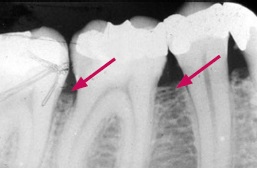

Røntgenbilleder kan vise, hvor fremskreden sygdommen er.

Normalt fæste

Røntgenbilleder af tænder med normalt fæste og tænder med fæstetab. Billederne er taget med fem års mellemrum af den samme patient.

Fæstetab